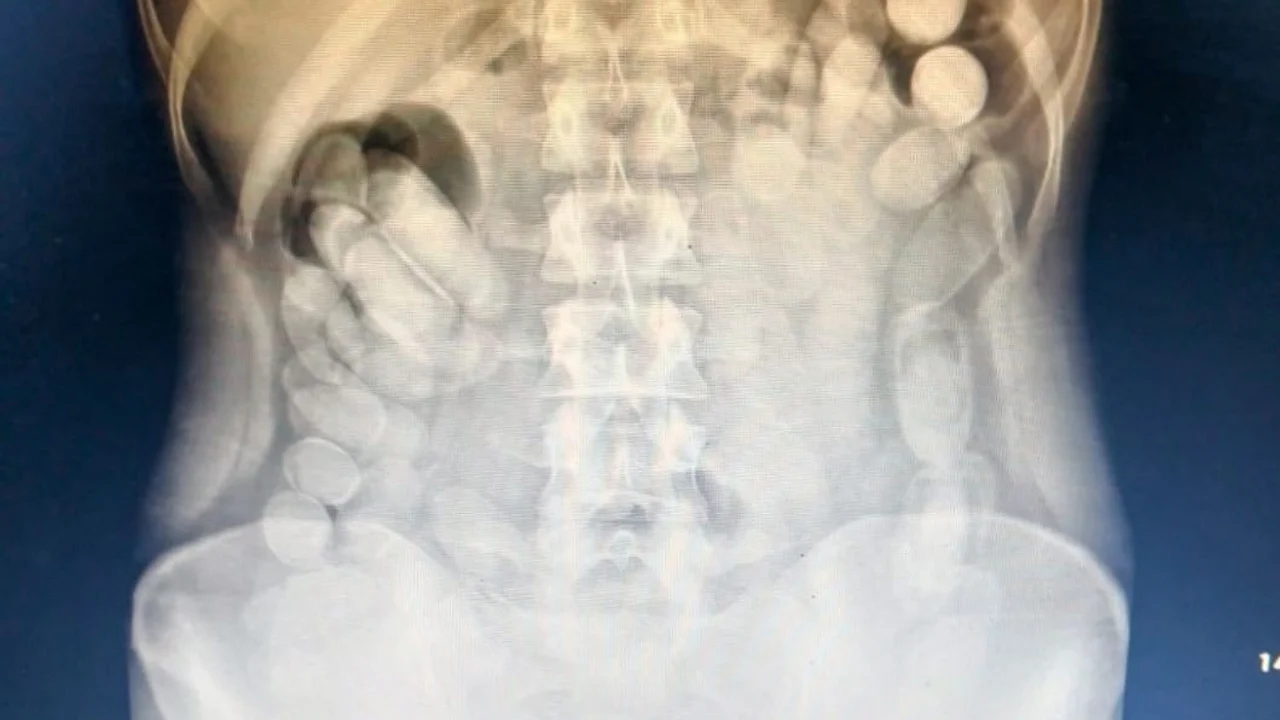

Una vez en el Nosocomio local, se le realizó una radiografía a la mujer mediante la cual se pudo observar la presencia de las dosis en su abdomen. Más tarde, la involucrada evacuó 106 cápsulas.

Tras realizar la prueba de campo Narcotest sobre los 118 envoltorios cilíndricos detectados se obtuvo un resultado positivo para cocaína con un peso total de 1 kilo 388 gramos.